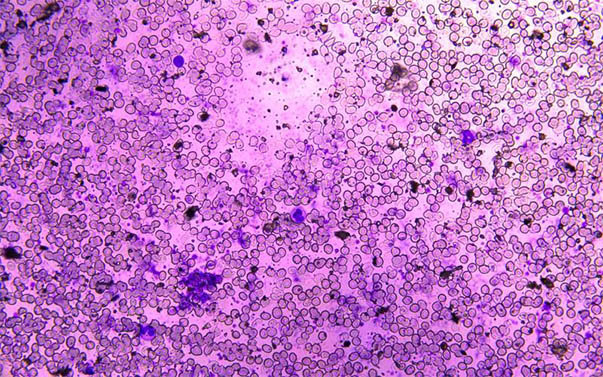

以下是明美生物显微镜下的血片-常规血形态观察(主要是拍摄血形态组织和观察白细胞的计数):

此次医院检验科使用的是明美生物显微镜ML31,采用无限远光学系统,可实现明场、暗场、相差多功能显微观察,调焦系统,同轴粗微调焦机构,机械式移动平台,平台尺寸210*140mm,移动范围76*50mm,外置1x数码相机接口,拍照视野大小和目镜视野同步实时显示